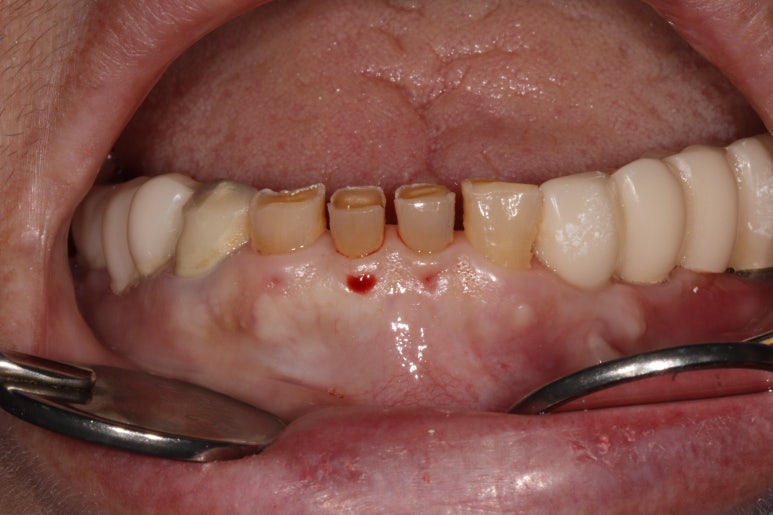

너무나 짧았던 아래 앞니를 회복해주기 위해 치관연장술(CLP)을 시행했습니다.

제가 전공한 치주과 진료 중 '잇몸성형'이라는 분야가 있습니다.

예쁘기 위한 잇몸 성형도 있지만, 기능적으로 필요에 의해서 하기도 하죠.

임시틀니를 껴드리면서 짧아진 앞니를 보상하기 위해서 약간의 공간을 띄워놓은 상태였어요.

그래야 짧아진 앞니를 제 크기로 만들 수 있겠죠?

저희는 치관연장술 (CLP, crown lengthening procedure)이라고 부릅니다.

대학병원 치주과 전문 진료기도 합니다. ㅎㅎ 일단 얼마만큼 잇몸을 제거할지를 표시해두죠.

간단하게 이해를 도와본다면, 이상적인 형태를 갖출 수 있도록 잇몸을 제거하고,

판막을 거상하여 하부의 치조골 조직 삭제 및 양형골 형태의 골형성을 시행합니다.

이 후 봉합을 시행하여 마무리!

아직 임시치아라 그 모양이 완전치는 않지만, 확실히 더 나아진 형태를 보이고 있네요!

어금니는 임플란트 임시치아로, 앞니는 자연치 임시치아로 지내고 계신 모습입니다.